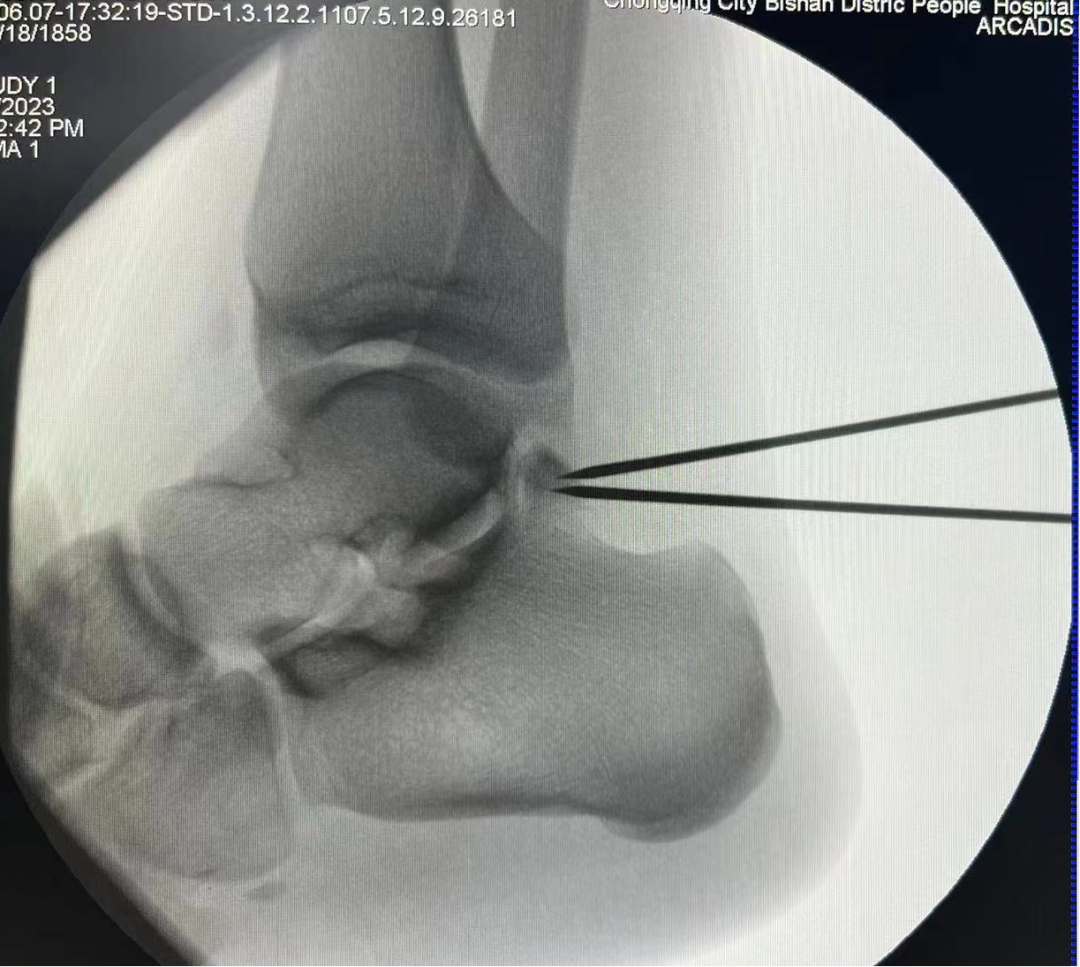

術中C臂定位病灶位置

一位19歲大學生,由于左踝長期疼痛,輾轉多家醫院癥狀未緩解,嚴重影響其學習生活,經人介紹來到我院骨科治療。骨科副主任(主持工作)彭李華博士為其進行了全面專業的檢查,發現為三角籽骨綜合癥。完善術前檢查及準備后,彭李華博士為患者行“踝關節全內鏡下清理、松解術”。患者對手術效果滿意,已順利出院。

踝關節鏡下手術是一種微創治療技術,其只有2-3個1cm左右的手術切口,在關節內鏡直視下進行手術操作,可以對踝關節進行全方位檢查,更直觀地發現問題、解決問題。相較于傳統手術,其具有創傷小、出血少、恢復快、美觀等優點。